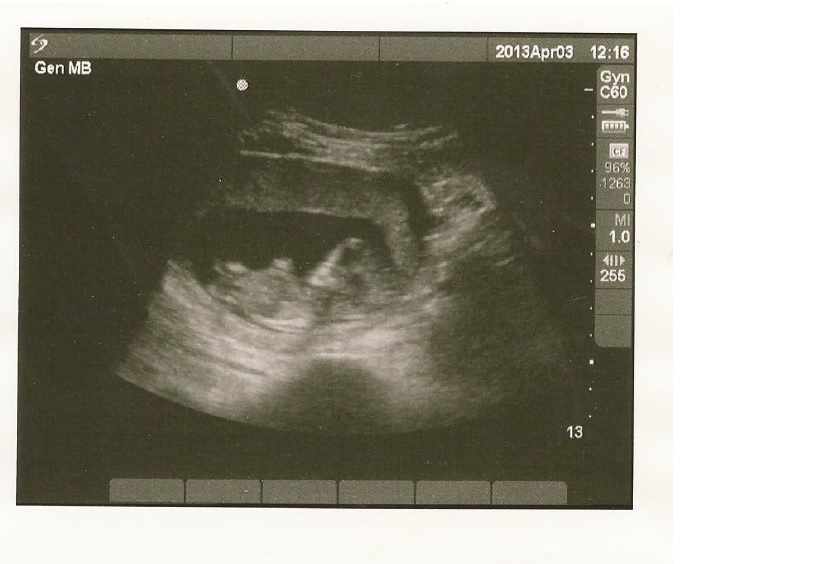

I had an ultrasound done yesterday at 12 weeks 2 days and would love some opinions. Thanks!

Not the best pic....but I'm going to lean boy aswell :)

Leaning boy as its not a great pic. Good luck x

I am no expert but I am not convinced that there is a nub showing